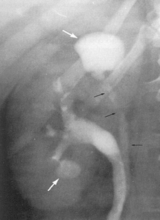

CANCERUL RENAL PROPRIU-ZIS produc boselarea localizata a conturului renal, uneori cu aspect neregulat, anfractuos. Tumorile mai mari, prezinta deseori calcificari amorfe, grosiere, neregulate, care se vad chiar la radiografia renala simpla. Examenul urografic va arata dislocari si compresiuni ale tijelor caliciale si calicelor, amprentari bazinetale. Tumorile ce se dezvolta medio-renal produc îndepartarea grupelor caliciale între ele - "semnul ghearei". Cancerul polului renal inferior determina o împingere mediana, spre coloana lombara a ureterului proximal.

Tumorile de dimensiuni mari, produc invazia sistemului pielo-calicial, moment care, urografic, se traduce prin amputarea calicelor si bazinetului, lipsa lor de umplere cu substanta de contrast, precum si lacune cu contur anfractuos, neregulat (în caz ca invadarea este doar marginala). Ureterul poate fi comprimat extrinsec de tumora renala si, uneori, chiar complet obstruat, ducând la imaginea de rinichi mut urografic.